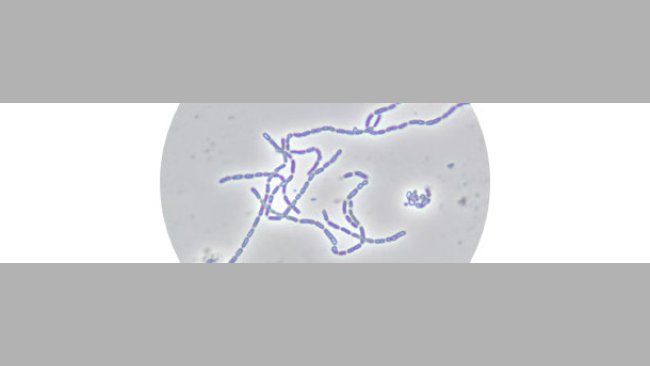

La administración de antibióticos puede determinar la presencia en el mercado de alimentos de origen animal con contenidos residuales de estas sustancias, bien del principio activo en su forma original o bien de sus metabolitos.